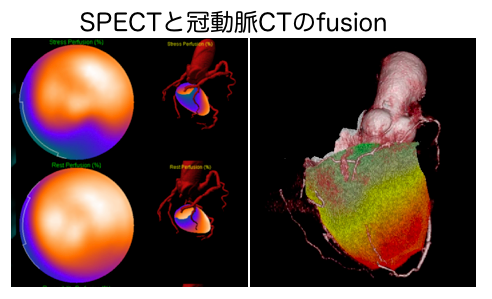

spectの画像